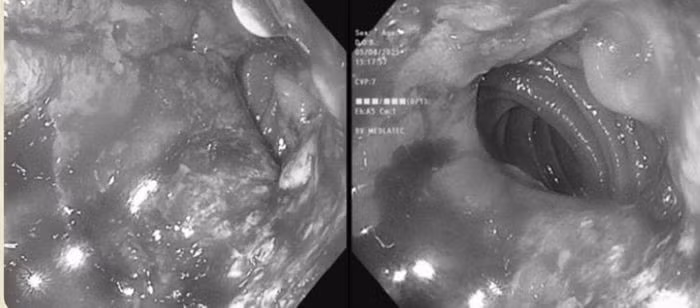

Kết quả nội soi dạ dày cho thấy dạ dày của ông đã bị cắt bán phần từ trước. Phần dạ dày còn lại và miệng nối bị phù nề, xung huyết, kèm theo nhiều vết loét dễ chảy máu khi bơm hơi. Các bác sĩ đã tiến hành sinh thiết bốn mảnh tại bờ ổ loét để xét nghiệm mô bệnh học.

Kết quả sinh thiết cho thấy các tuyến dạ dày có dấu hiệu bất thường: Nhân tế bào lớn, kiềm tính, màng nhân méo mó, hạt nhân nổi rõ. Dựa trên những phát hiện này, bác sĩ chẩn đoán ông M. mắc ung thư biểu mô tuyến dạ dày.

Ngoài ra, xét nghiệm Cellblock từ dịch ổ bụng phát hiện nhiều đám tế bào biểu mô với nhân lớn, màng nhân méo mó, chất nhiễm sắc thô, cấu trúc sắp xếp gợi ý carcinoma di căn.

Tổng hợp các kết quả cận lâm sàng, bác sĩ kết luận ông M. mắc ung thư dạ dày di căn phúc mạc. Sau chẩn đoán, ông được tư vấn chi tiết về phương án điều trị và lộ trình chăm sóc trong thời gian tới.